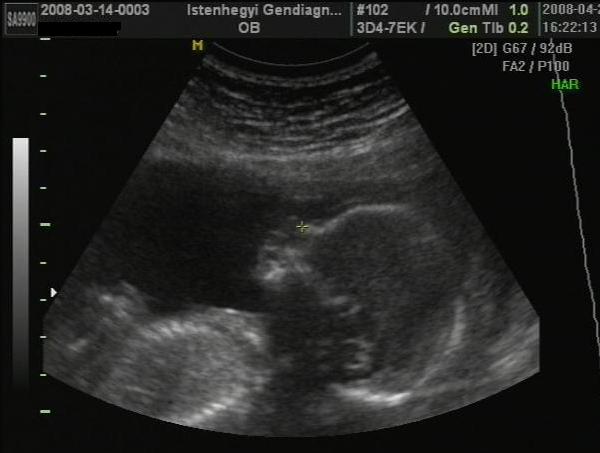

Kép

A nyilacska mutatja a lényeget, alulról készült a kép, "pelenkázó pózban" ahogy a doki bácsi mondta...